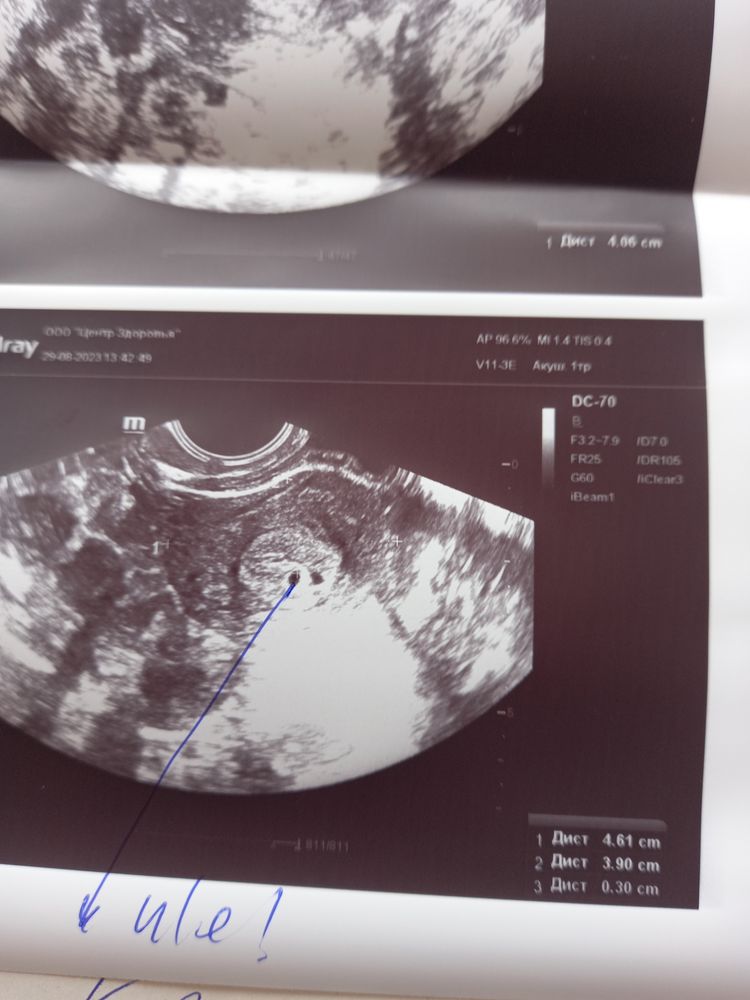

Девочки похоже ра 2 плодных яйца иль мне кажется. П.я.3 мм.при гхч 860 что думаете?

это жидкость между листками эндометрия. Так бывает. Потом перестанет визуализироваться